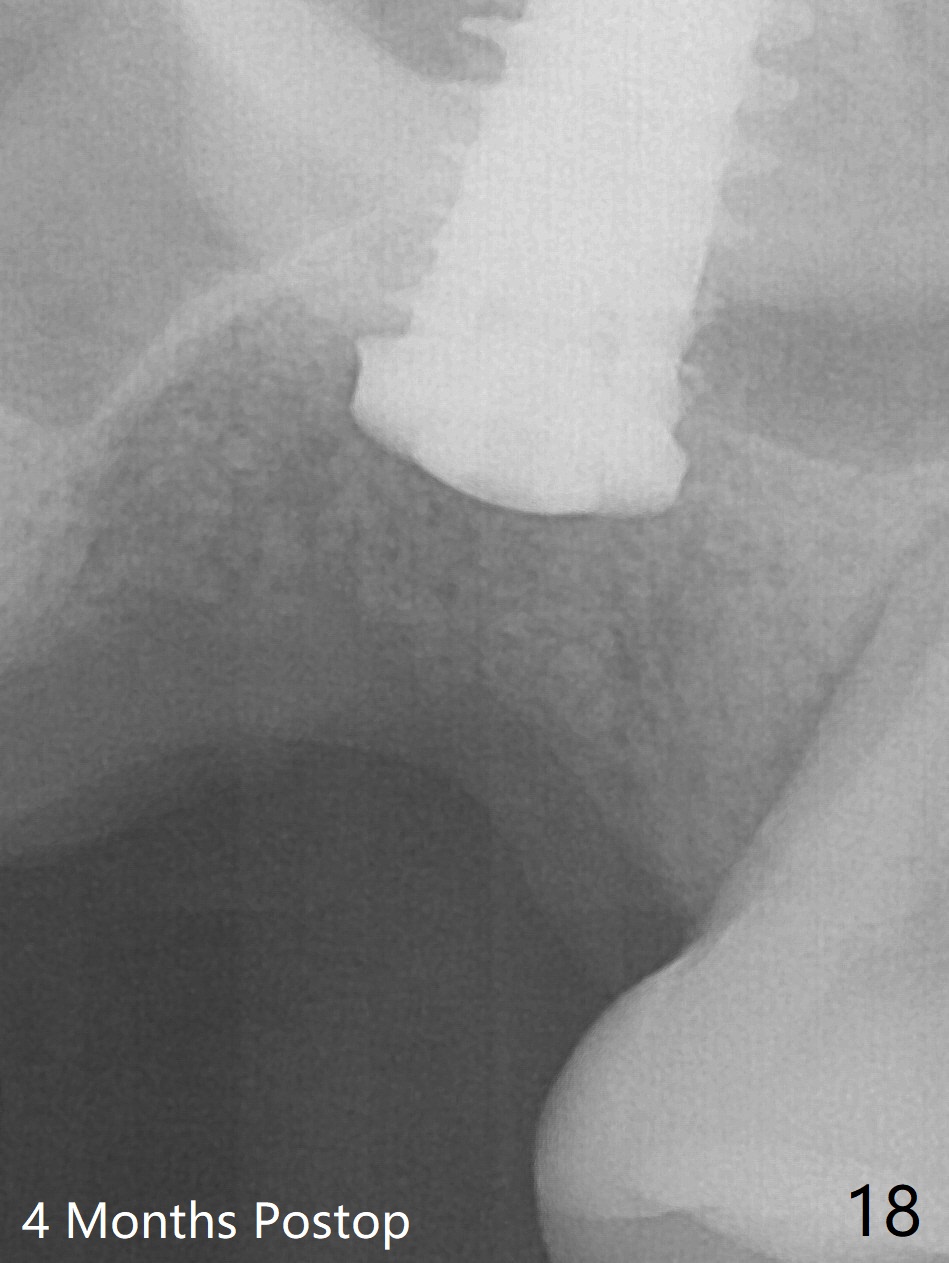

Poor visibility for immediate implant in the molar region is another contributing factor for the dislodgement.  The patient returns for follow up 15 days (Fig.15) and 1 month (Fig.16) postop.  Bone graft seems to be stable around the implant.  The socket heals 4 months postop (Fig.20).  The implant seems to have been osteointegrated (Fig.17,18).  It will be backed up for ~ 3 mm to improve implant/crown ratio (Fig.19, as compared to Fig.14).  If it cannot be done, take impression immediately and make a subgingival provisional before suturing.

In fact, there is no coronal bone for the implant to be backed up.  Therefore, impression is taken after uncover and insertion of a 5.5x5.7(4) mm abutment.